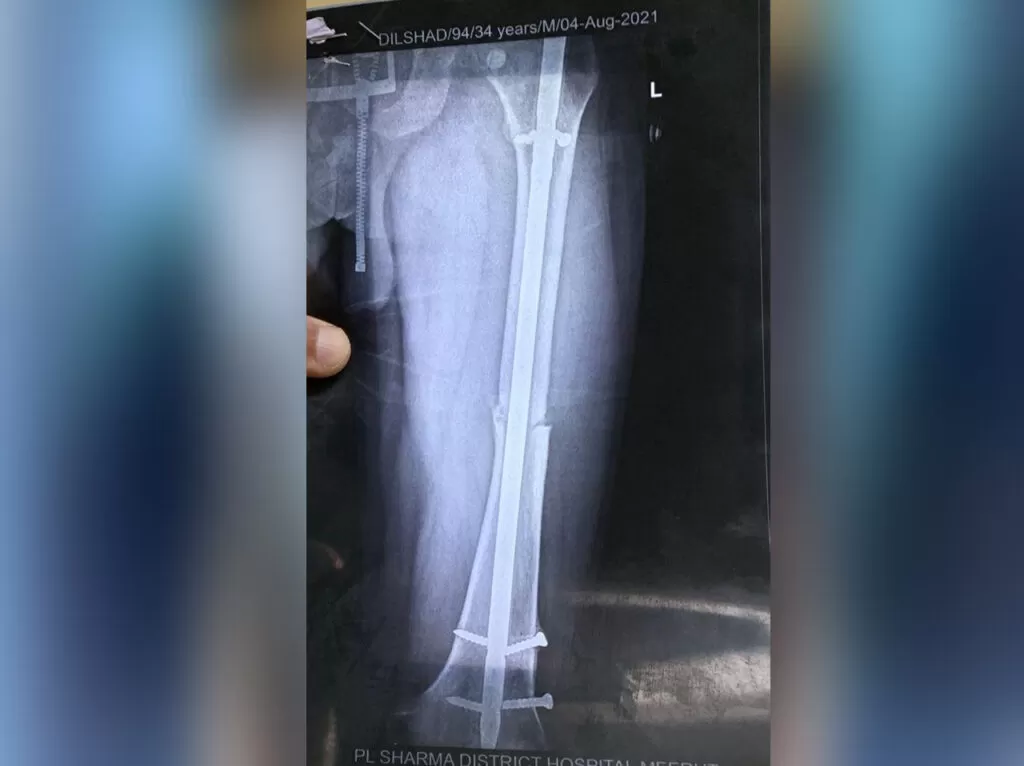

Mr. Dilshad

Name: Mr. Dilshad

Date of Operation: 10 May 2021

Age: 32 Years

Complex Trauma